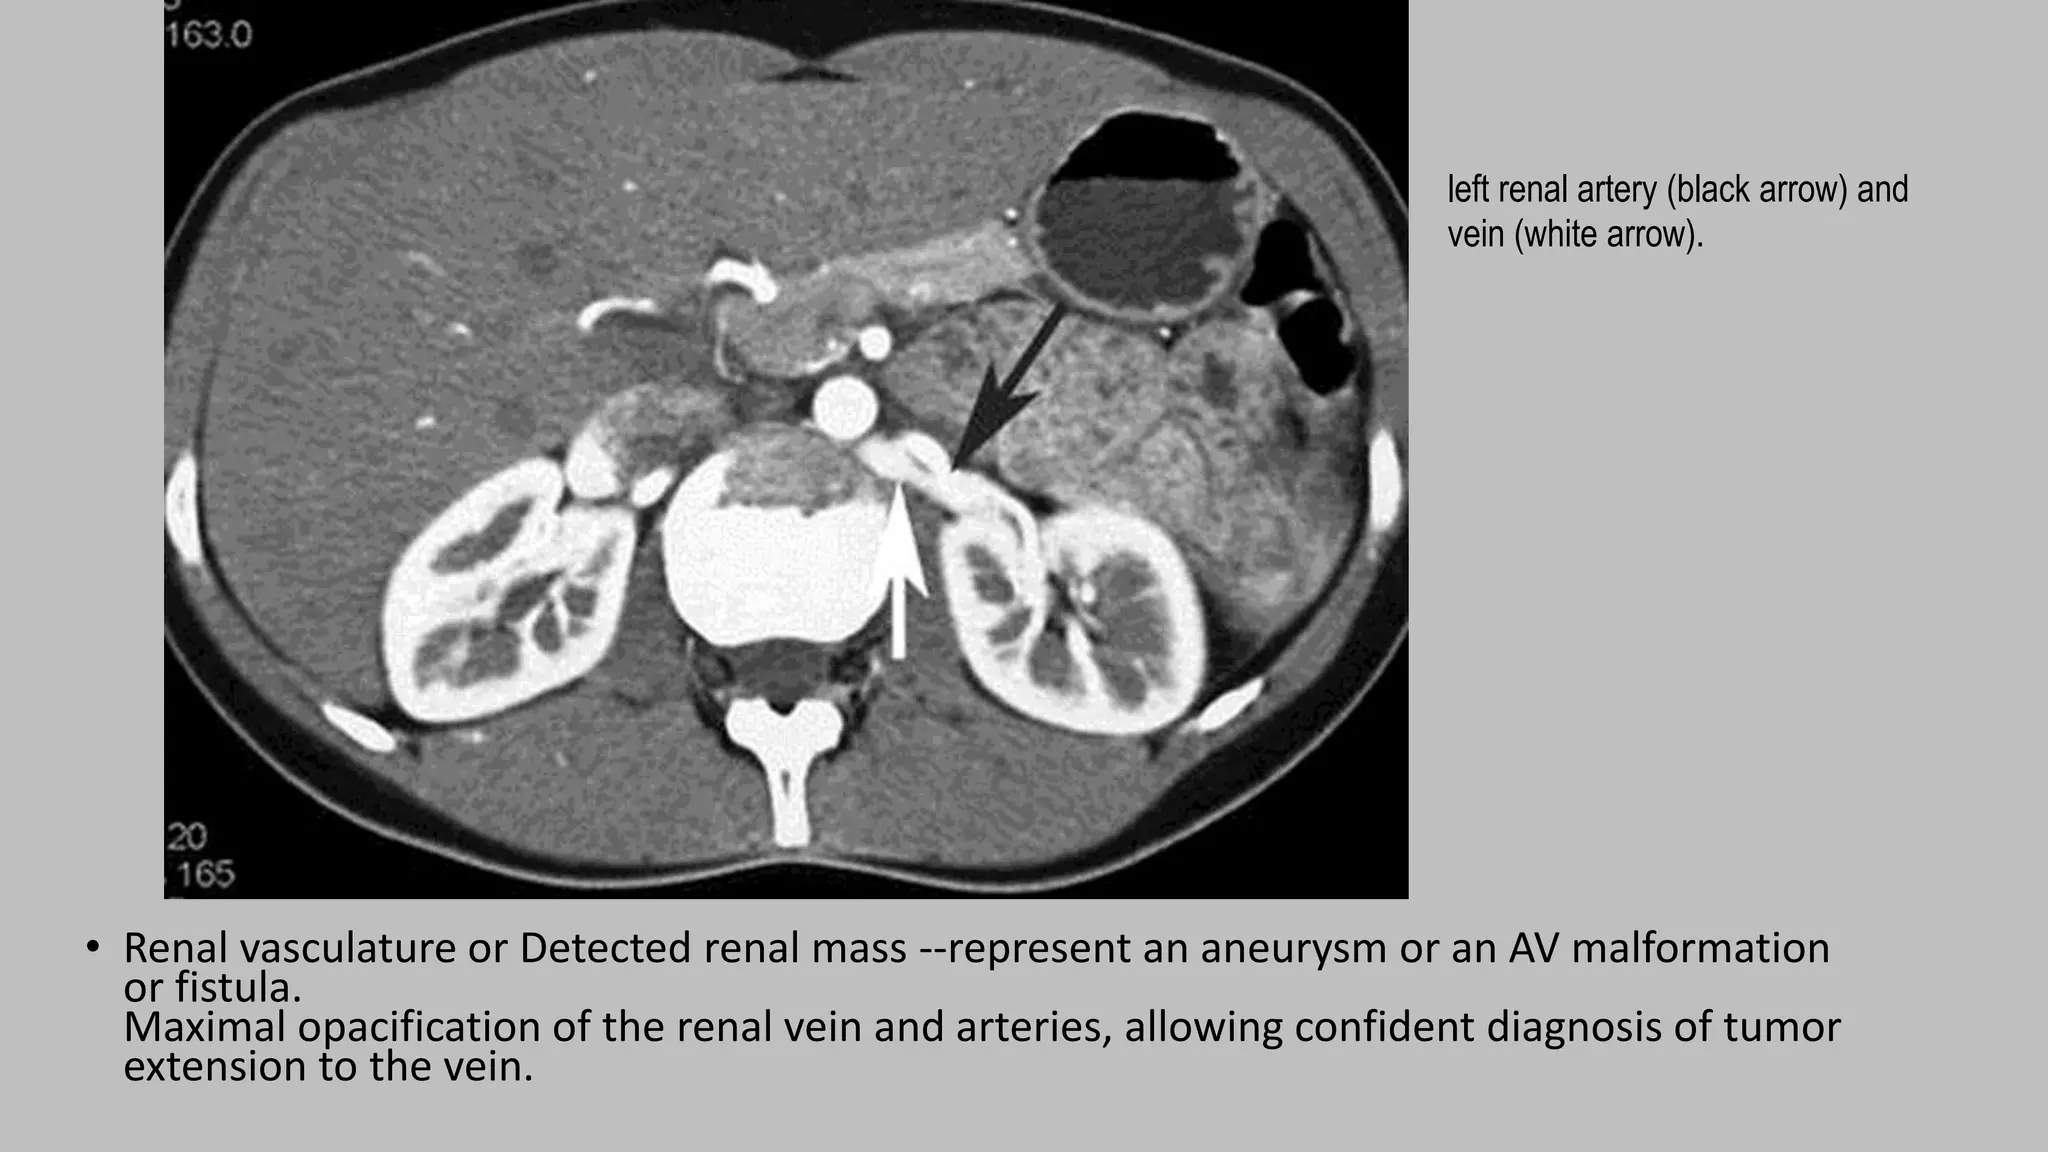

• Renal vasculature or Detected renal mass --represent an aneurysm or an AV malformation

or fistula.

Maximal opacification of the renal vein and arteries, allowing confident diagnosis of tumor

extension to the vein.

left renal artery (black arrow) and

vein (white arrow).